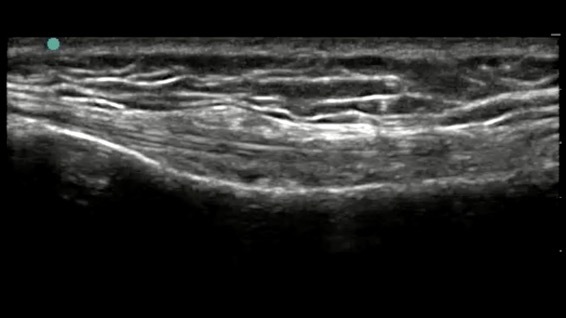

Knee Pes Anserine Anatomy Image